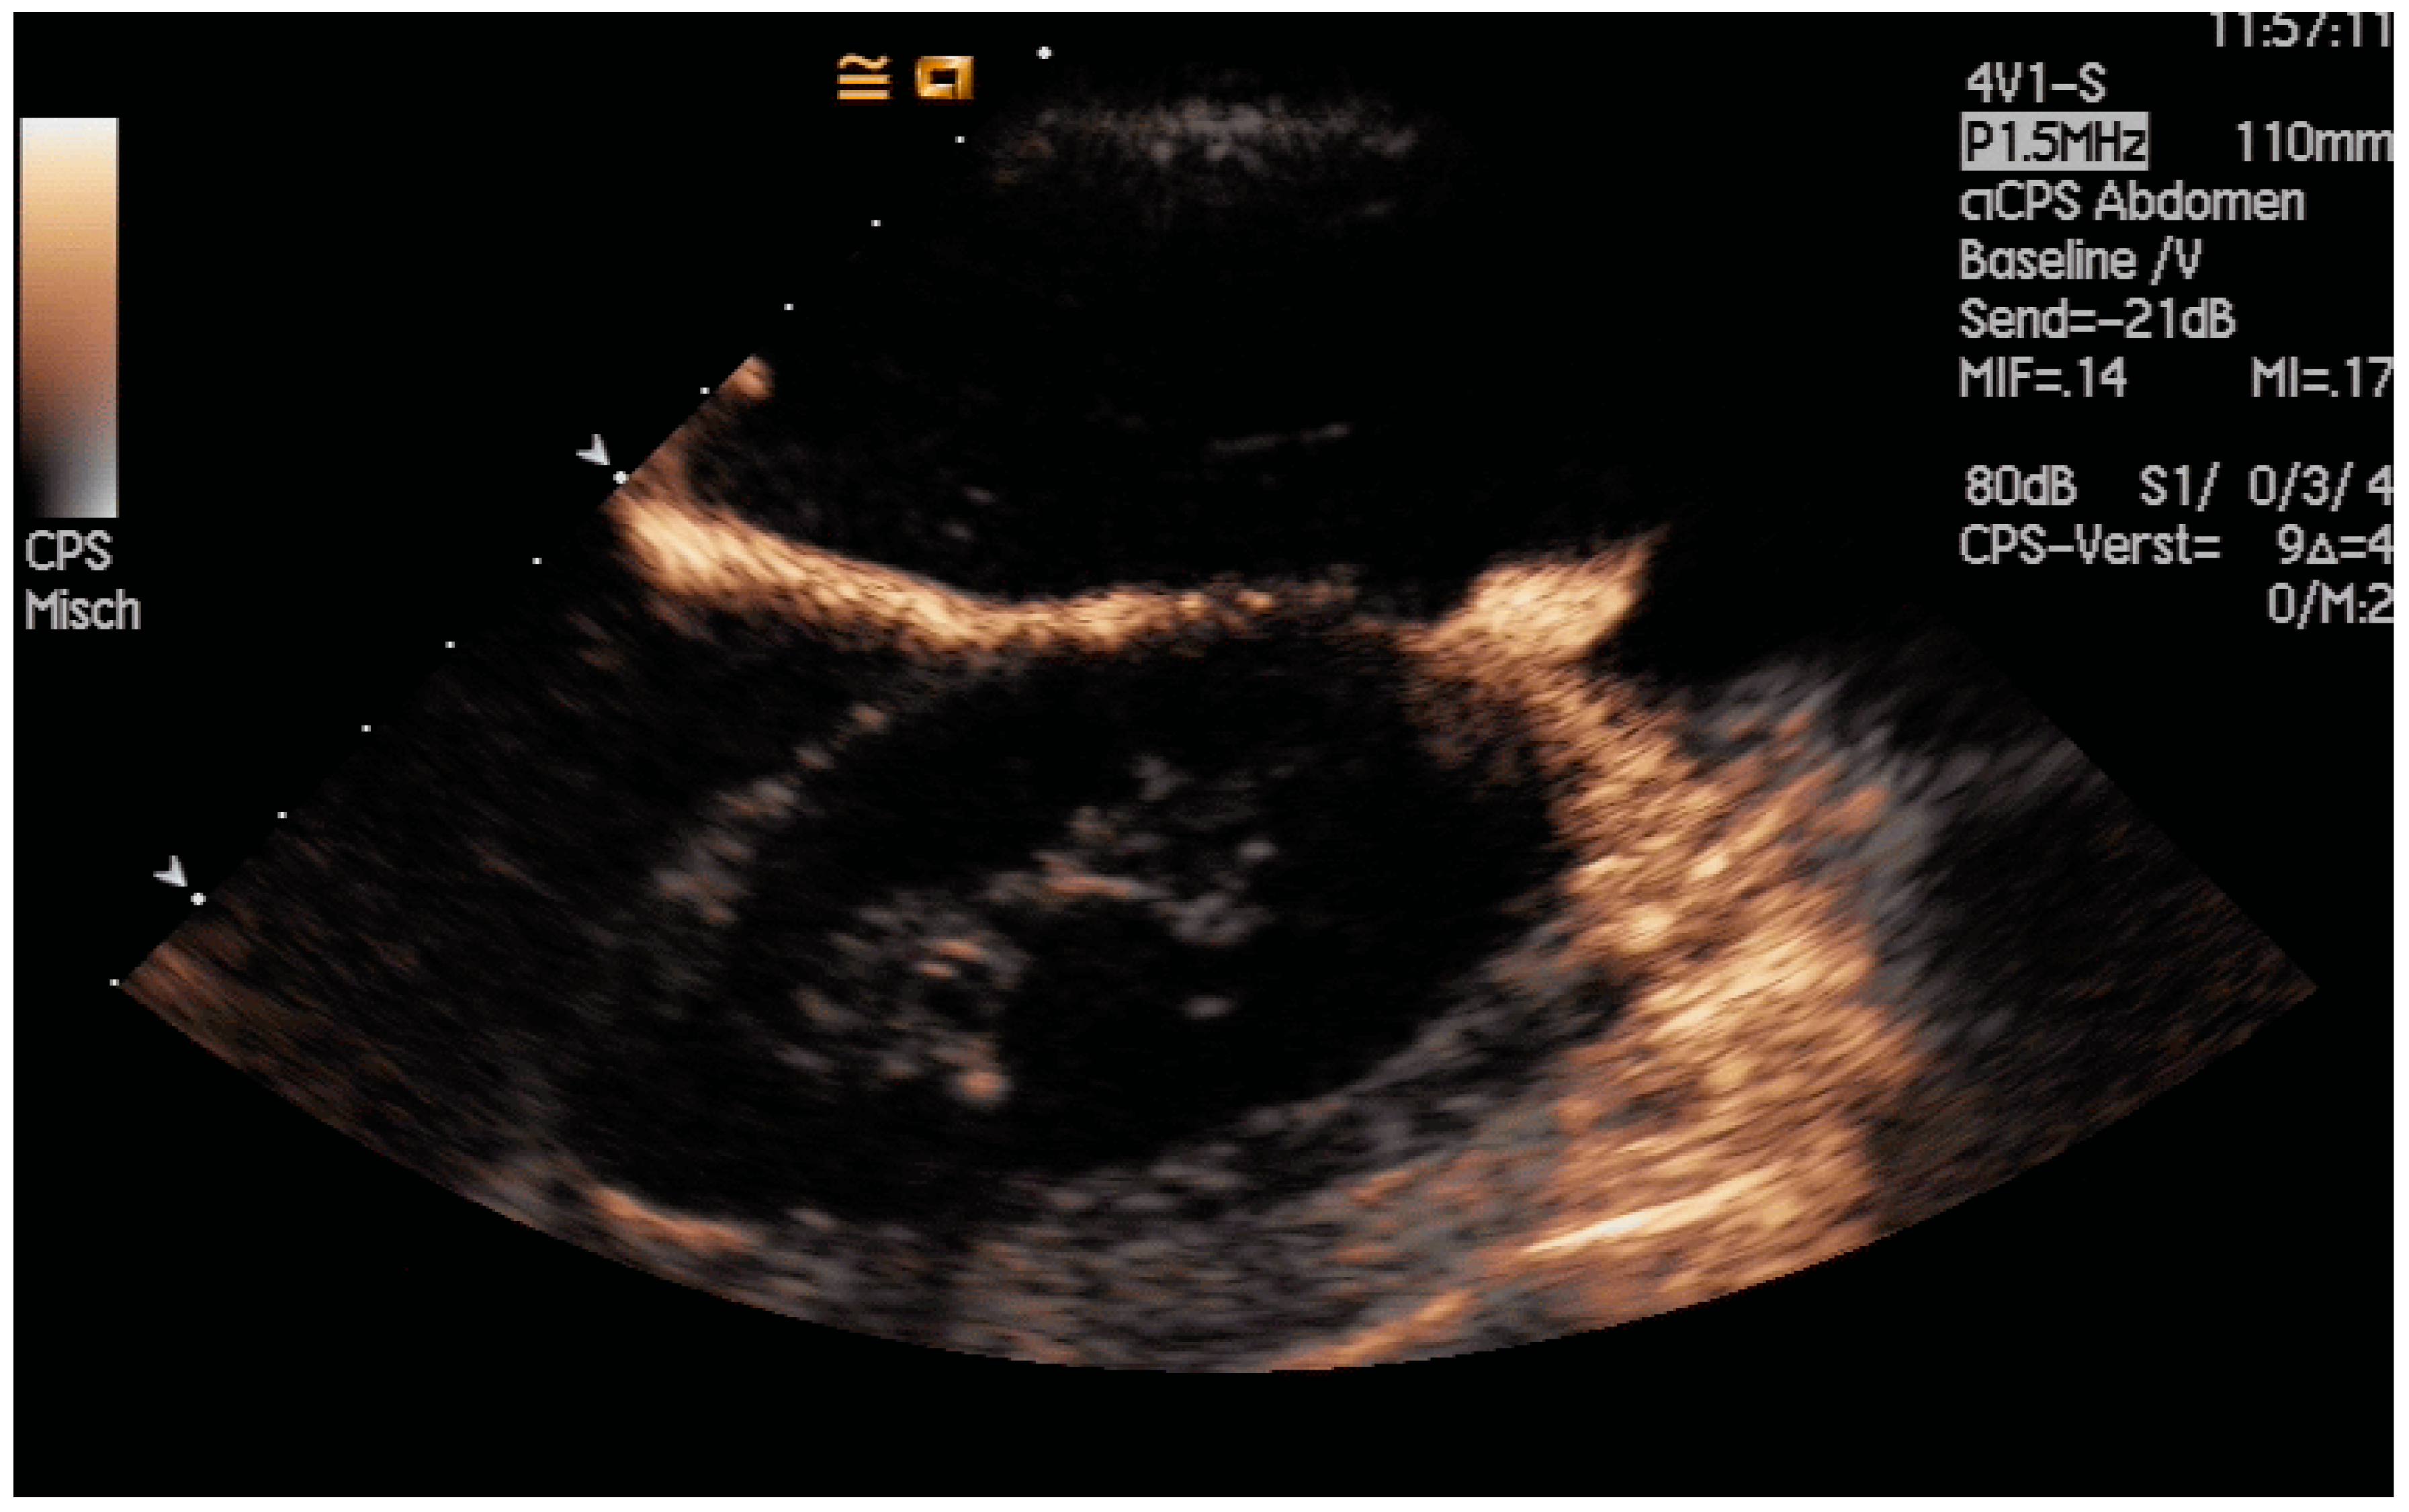

The application of diluted US contrast agents such as SonoVue® can confirm correct needle placement as well (Figure 7) but will worsen guide-wire visibility thereafter.

Figure 7.

After injection of one drop of SonoVue® diluted in 10 mL sodium chloride 0.9%, the dilated intrahepatic bile ducts are depicted, and correct needle placement is confirmed. However, subsequent monitoring of the guide wires will be hindered.